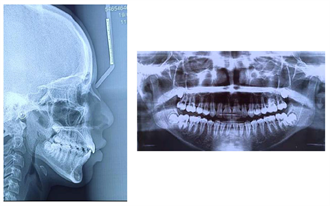

A 12-year-old patient presented to the dentofacial orthopedics department of the Dental Consultation and Treatment Center (CCTD) of the CHU Ibn Rochd of Casablanca, Morocco, with a mainly aesthetic complaint related to the projection of the maxillary incisors. The functional examination showed an atypical swallowing with tongue interposition. The clinical examination (Figure 13) showed a convex profile with an accentuated mentolabial groove and a short cervico-chin distance. The patient was at the stage of young adolescent dentition. Regarding the inter-arch relationship, we recorded a class II molar and

canine relationship, with 6 mm of overjet and 4 mm of overbite. He had a diastema between 11/12/13/21/22/23. The panoramic radiograph (Figure 14) showed normal bone and tooth shapes, with the presence of the 4 wisdom tooth sprouts. Cephalometric analysis (Table 3) revealed a class II skeletal base (ANB = 5˚) with a protrusive maxilla, a retrusive mandible (SNA = 83˚, SNB 78˚). In addition, the patient had a skeletally long face (GoGn/SN = 41˚, FMA = 35˚). In addition, the upper incisors were proclined (I/NA = 37˚/10mm), and the lower incisors were also proclined (I/NB = 36˚/8mm).

Figure 14. Pre-treatment lateral cephalogram and panoramique radiograph.